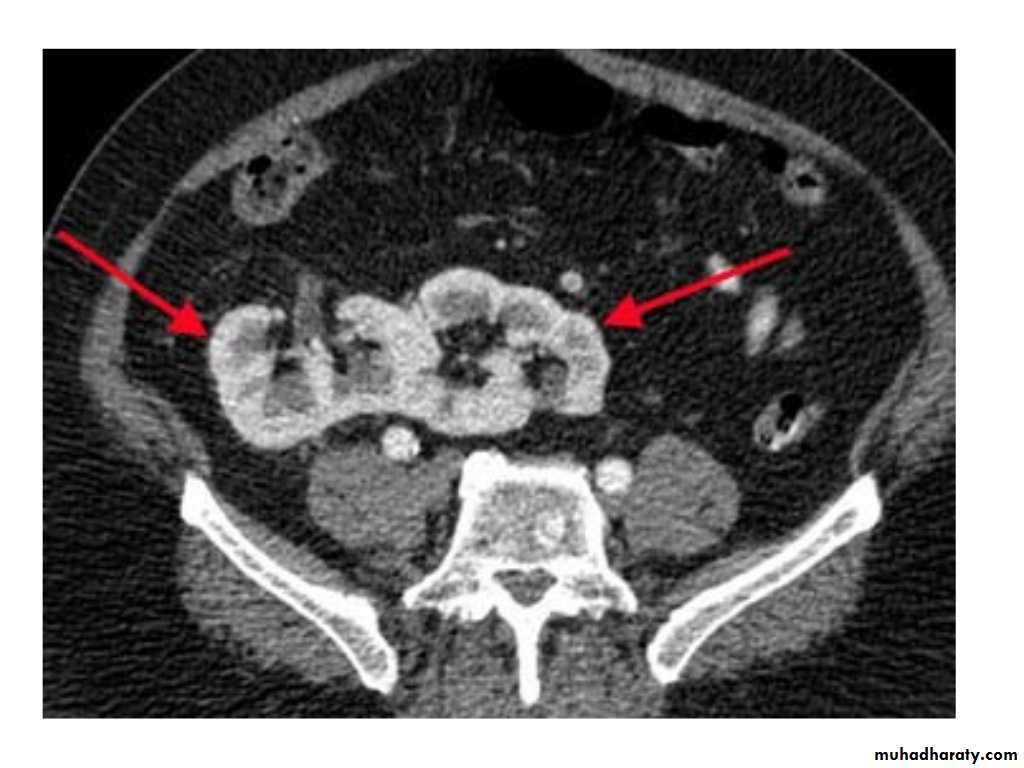

IVU shows

1. The kidneys at low position .2.Close to the spine with long axis parallel to the spine

3. Malrotation manifested by medially directed calyces.

4- The renal pelvis and ureters are anterior and lateral in position.

5- Hydronephrosis and calculi highly associated.